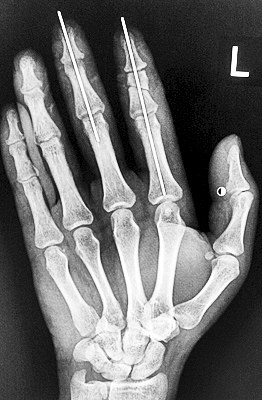

術(shù)后X光顯示,骨骼對位良好。

在經(jīng)過兩個多小時手術(shù)后,早上8時許,盧微波下令松止血帶,數(shù)十秒后男子蒼白的食指逐漸紅潤起來,食指在離體10個小時后恢復血運。

緊接著,盧微波又開始中指再植手術(shù)。上午10時許,中指在離體12小時后也成功恢復血運。